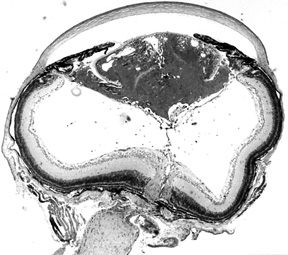

Figure 1d. Higher power view of lens in Fig. 1c.

The lens has a nucleus with non-nucleated fibers, but these are disorganized.